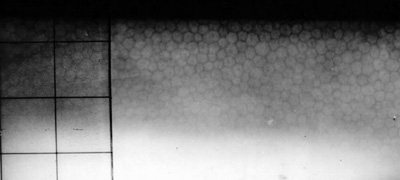

Fotos 1 - Picadura en el Limbo temporal

Postoperatorio con edema de córnea que fue cediendo progresivamente. - Polo posterior sin alteraciones.- Tensión Ocular 12 aplanático de Goldman

A los 5 meses: Refracción: AVsc 1.00 +0.50 esférico AVcc 1.00. Discreto engrosamiento corneal en creciente, inferior-temporal. - Despigmentación del Iris, pupila normoreactiva. Tensión ocular 12 aplanático de Goldman.

Último control a los 24 meses. Refracción: AVsc 1.00 +0.75 esférico AVcc 1.00. Subjetivamente Bien. - Creciente corneal inferior engrosado con mayor textura en la Descemet. (Foto No2)

Foto 2 - Ultimo control a los 24 meses